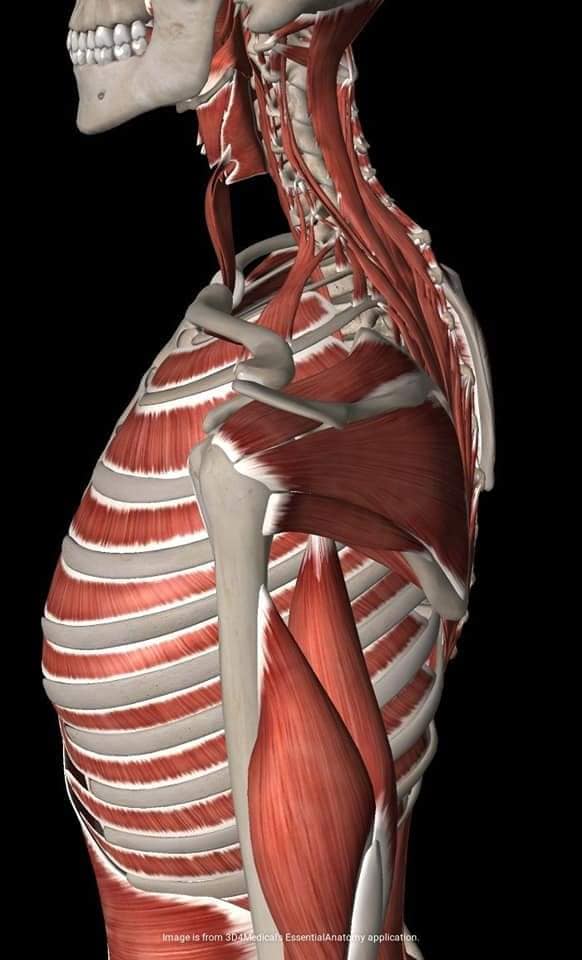

Спинні м'язи

Спинні м'язи виконують функції підтримки хребта, а також дозволяють здійснювати рухи тулуба.

Поверхневі спинні м'язи

М'язи, що піднімають лопатку: Трапецієподібний м'яз: великий м'яз, що покриває верхню частину спини. Його функція - підтримка і рух лопаток, а також забезпечення стабільності хребта.

М'язи, що ведуть лопатку до хребта: Широкий м'яз спини: великий м'яз, що розташований в нижній частині спини. Він відповідає за рухи плечей і лопаток, а також за розширення верхньої частини тулуба.

Глибинні спинні м'язи

М'язи, що забезпечують стабільність хребта: М'язи, що розташовані між хребцями: включають мускулатуру, яка забезпечує стабільність і підтримку хребта, а також дозволяє здійснювати рухи хребта.